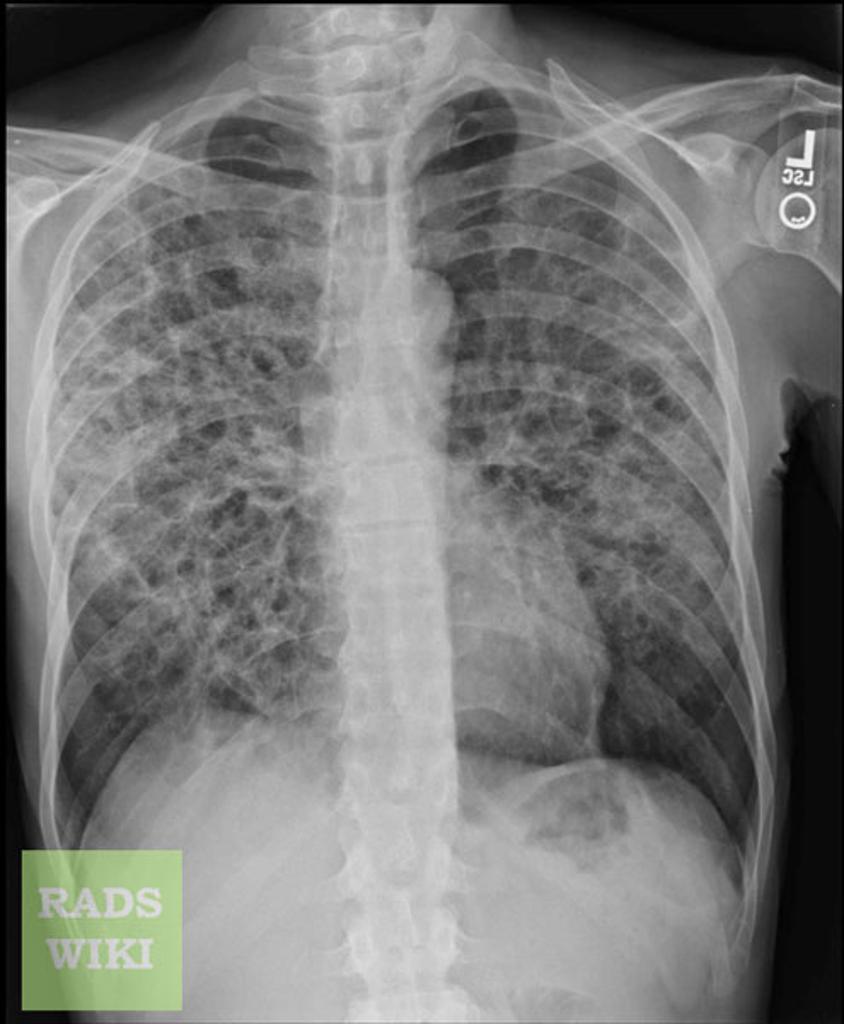

What is going on in this radiograph?

PCP pneumonia

This sort of very diffuse reticular pattern is highly suggestive in the right clinical context, and you might consider ordering an HIV test.